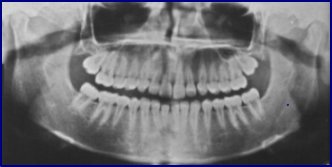

ortopantomografia

Antes de mais importa referir que existem vários tipos de radiografias, cada um com diferentes fins. Na Clínica GALIZA, realizamos por sistema a todos os novos pacientes uma "ortopantomografia" (radiografia panorâmica), na qual se visualizam os maxilares, seios paranasais, dentes e outras estruturas, e que nos permite detectar cáries, fracturas e lesões ósseas e dentárias, quistos, granulomas, dentes impactados e imensas outras patologias, não perceptíveis pelo simples exame clínico do paciente

Noutro âmbito existem as radiografias "periapicais", que abrangem apenas alguns dentes e que servem para ver detalhadamente as lesões previamente detectadas, diagnosticar cáries, avaliar doenças periodontais (gengiva, ligamentos e osso que envolve o dente), etc.

Temos ainda as "cefalometrias de crânio", cujas principais funções são avaliar o crescimento e relações entre os maxilares e destes com a base do crânio, tendo a sua principal aplicação em ortodontia (especialidade que move os dentes por meio de aparelhos para posições funcional e esteticamente correctas).

Por último e apenas em casos muito específicos pode ser necessário realizar outras técnicas como TC (tomografia computadorizada), ou RMN (ressonância magnética nuclear).